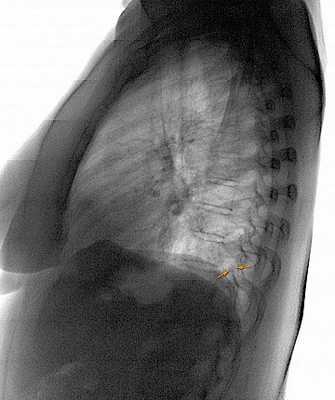

- Рентгенодиагностика. При проведении ЭРХПГ выявляются изменения протокового аппарата, вызванные образованием рубцов. Для подтверждения диагноза может проводиться КТ поджелудочной железы.

- Пункционная биопсия. Если данный метод диагностики не дает необходимой информации, выполняется биопсия поджелудочной железы, которая является «золотым стандартом» диагностики фиброза поджелудочной железы и позволяет получить достоверные данные о морфологических изменениях органа.